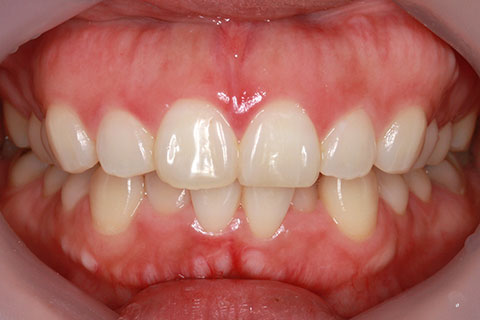

ハーフリンガル矯正4:上の歯のみ舌側矯正で治療(矯正期間24ヶ月)

- 年齢・性別

- 23歳女性

- 治療期間

- 2年0ヶ月

- 抜歯

- 上下4番抜歯

- 治療費

- 110万円

- 備考

- マルチブラケットを用いた矯正治療

- 治療内容

- 施術の副作用(リスク)

- 表側矯正と比較して、前歯のラビッティング(舌側傾斜)を起こしやすい。